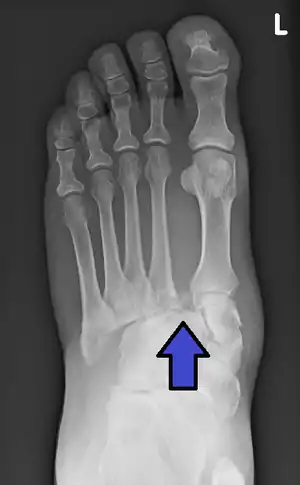

| Lisfranc fracture | Jacques Lisfranc de St. Martin | fracture dislocation of midfoot | forced plantar flexion of foot or dropping heavy weight on foot | Lisfranc fracture at Who Named It? |

|